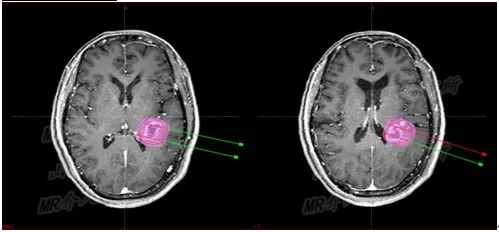

3D打印模板术中定位

但是磁共振+3D打印模板+I125粒子植入的创新组合,却是史无前例。

根据满女士的治疗计划,李成利主任找专人制作了颅脑介入手术专用的3D打印引导模板。

介入手术治疗中,

磁共振实时引导技术保证介入手术过程在可视化下连续性完成

手术过程仅半小时,先对满女士进行局麻,然后在1.0T开放式介入磁共振监控及3D打印模板引导下,

李成利主任将4根磁共振兼容性穿刺针平行穿刺至肿瘤病变既定位置,根据近距离放疗计划植入I125放射性粒子,

该粒子通过持续释放低剂量γ射线对肿瘤细胞起到杀伤作用,而且对周边正常脑组织损伤较小。

术中磁共振显示,4根穿刺针平行准确穿刺至病灶内